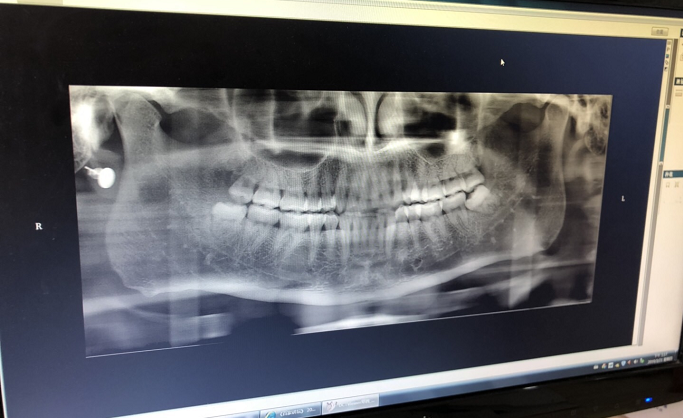

小編因智齒導致牙齦腫痛被困擾很多年了,每年都要有那么兩三次,前兩天實在是忍無可忍,痛定思痛決定把四顆智齒一次性解決掉,一勞永逸。最后,小編現在是哭著在寫這邊軟文的,因為麻藥過后那個痛啊T-T....兩顆下面的智齒被拔掉后還被縫了兩針,還好小編只有4顆智齒(捂臉)。因為拔牙縫針,傷口表面是在口腔內,到底需不需要碘伏消毒液進行消毒呢?一般來說,如果沒有明顯的癥狀,其實是不需要的。但是為了讓自己安心放心,進行局部消毒也是可以的。